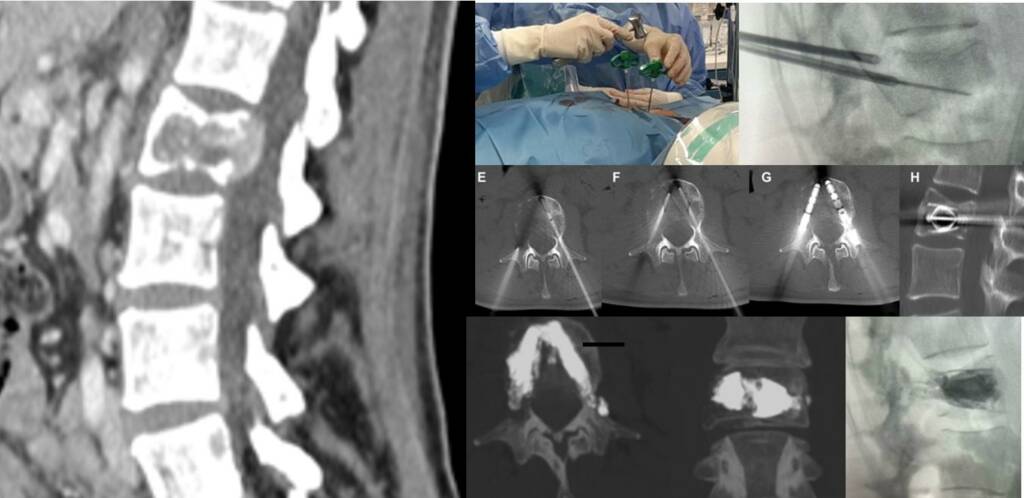

Procedure

Performed under conscious sedation or general anesthesia, the procedure includes:

Percutaneous transpedicular access

Implant positioning and expansion within the vertebral body

- Adjunctive cement injection for stabilization